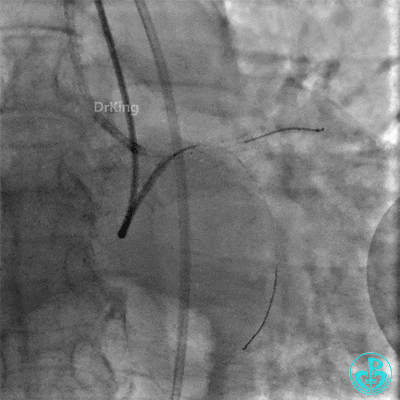

撤回逆向导丝及微导管造影,钝缘支远端侧支造影剂渗漏,局部造影剂滞留范围不断扩大。

前降支末梢经微导管释放3.0×2.5mm弹簧圈封堵破口。

钝缘支经微导管释放5.0×5.5mm弹簧圈封堵破口。